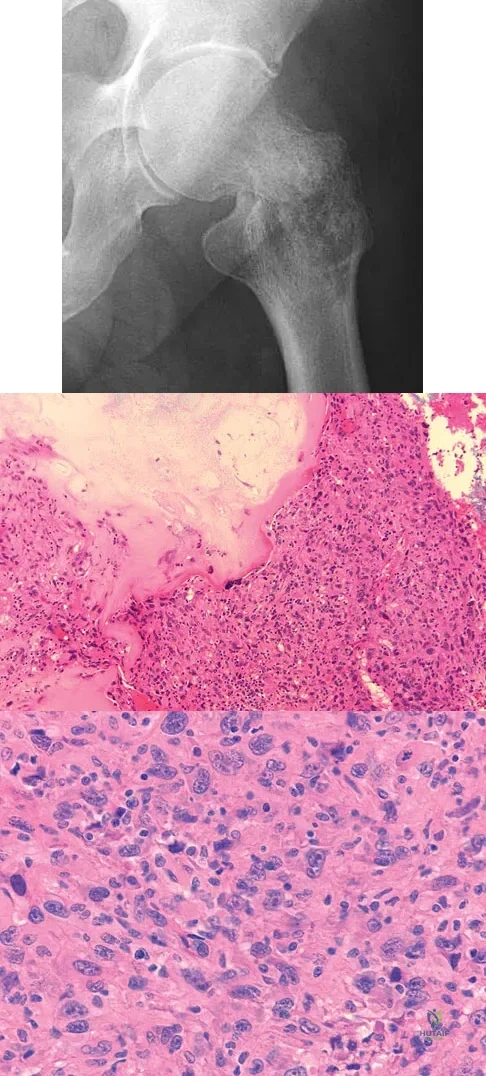

A 73-year-old man stepped off a street curb and felt a crack in his left hip. He is now unable to bear weight. A radiograph is shown in Figure 54a. Biopsy specimens are shown in Figures 54b and 54c. What is the most likely diagnosis?